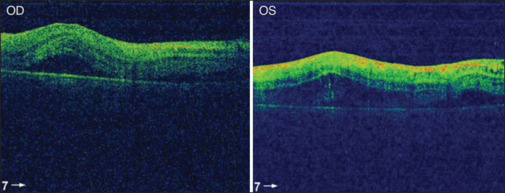

Purtscher retinopathy is a hemorrhagic and vaso-occlusive vasculopathy that results from head trauma. Typically, patients present with sudden onset of painless reduction in visual acuity and a group of retinal findings including retinal hemorrhages, retinal whitening, and optic disc edema. The objectives of the study were to describe the rare occurrence of combined central retinal artery and central vein occlusion in a child with Purtscher retinopathy and to illustrate the course of visual recovery and anatomical changes over 6 months of follow-up. The data were collected from the patient file including circumstances of presentation, visual acuity, anterior segment examination, fundus photography, fundus fluorescein angiography (FFA), B scan ultrasonography (B scan), and optical coherence tomography (OCT). Follow-ups over a 6-month period with repeated imaging were documented. A 6-year-old boy presented with a complaint of bilateral vision loss which occurred 2 days after falling out of high bed. On examination, visual acuity was hand motion bilaterally. External and anterior segments exhibited regular examination, apart from traumatic iritis in both eyes. Posterior segment examination showed intraretinal hemorrhages, retinal whitening bilaterally, and exudative retinal detachment, which was confirmed by OCT and B-scan. FFA of both the eyes showed delayed arterial and venous filling with macular hypoperfusion. Comprehensive systemic workup including brain imaging, hematology, immunology, and uveitis screening was negative. The patient was treated with a high-dose oral steroid. Six months later, his vision improved to 20/40 OD and 20/28 OS. Fundus examination and OCT showed peripheral retinal atrophy but preserved subfoveal outer retinal layers, which explained the visual improvement. Treatment with corticosteroids seems to be effective in reducing retinal edema and hastened visual recovery in patients with Purtscher retinopathy. Cilioretinal artery sparing can preserve the central vision in cases with combined artery and vein occlusion.